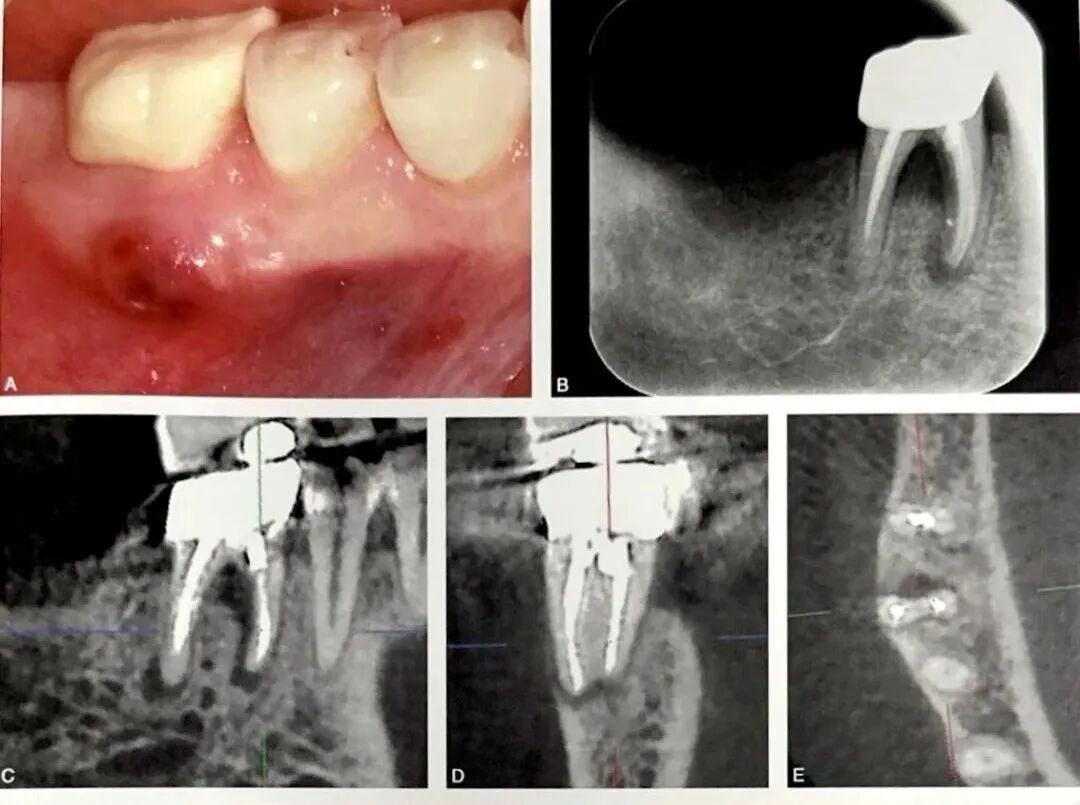

图1 右下颌第一磨牙近中根根裂。A为口内像示右下颌第一磨牙颊侧根尖区窦道;B为根尖片,示近中根根管充填良好,根周透射影;C为CBCT失状位;D为CBCT冠状位;E为CBCT水平位,示近中根根尖以及根周骨质破坏、颊侧骨板缺损;F为右下颌第一磨牙行显微根尖外科手术,切开翻瓣牵拉,见近中根颊侧骨板缺损;G为染色探查,近中根见贯穿牙根全长的颊舌向根裂线